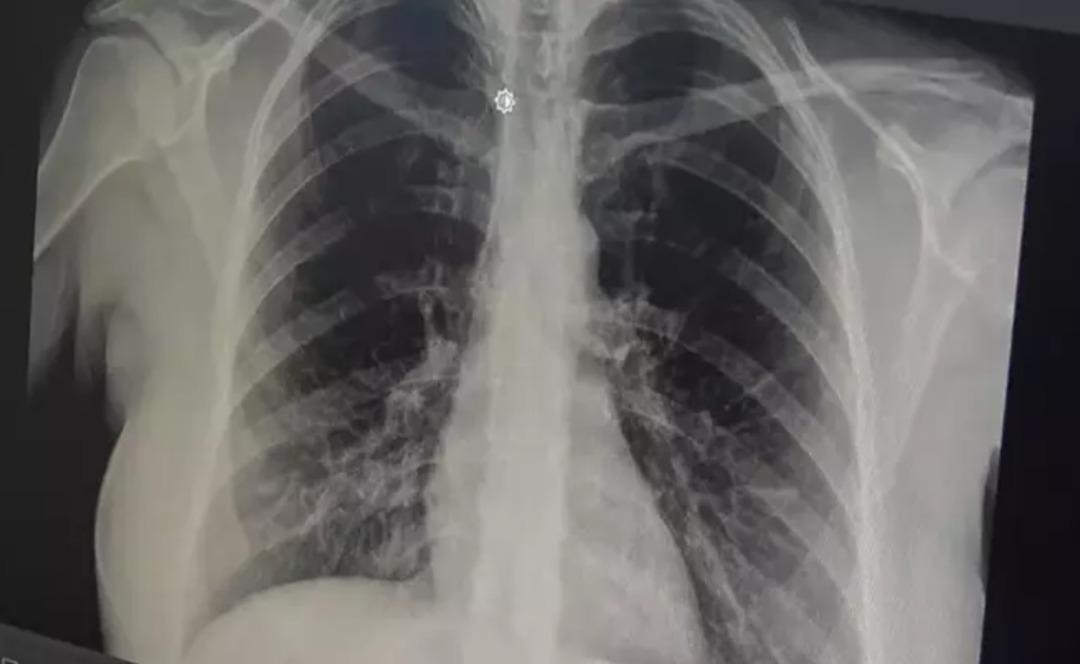

prof. Akut bronşitin solunum yolu virüslerinin neden olduğu bir hastalık olduğunu belirten Dr. Özlü, şöyle konuştu: “Günümüzde çok sık gördüğümüz bir hastalık. Genelde hastalar şöyle tarif ediyor: 'Öncelikle boğazım ağrıyordu, boğazım ağrıyordu. hafif ateş, burun akıntısı, hapşırma, geniz akıntısı ve öksürük: “2-3 gündür göğsümdeydi. Nefes alırken acı hissediyorum. İçeride bir çalı varmış gibi görünüyor. Nefes aldığımda göğsüm oraya sıkışıyor” çünkü bu aslında doğru. “Bronşit, solunum yolu virüslerinin neden olduğu bulaşıcı bir hastalıktır. Bu enfeksiyon üst solunum yollarıyla sınırlı olmayıp alt solunum yolları ve bronşları da etkiler. “dedi.

Akut bronşitin en önemli belirtisinin öksürük olduğunu vurgulayan Prof. Dr. Tevfik Özlü, “Kuru öksürük veya balgamlı öksürük şeklinde kendini gösterebiliyor. Bazen belirti daha çok hırıltılı solunum ve nefes darlığı şeklinde hissedilebiliyor. Yüksek ateş genellikle herhangi bir rahatsızlığa neden olmaz ancak bazen bakteriyel enfeksiyonlar da ortaya çıkabilir” dedi.

Bronşitin genel olarak hafif bir hastalık olduğunu ancak belirtilerin artması durumunda doktora başvurulması gerektiğini belirten Özlü, şöyle konuştu: “Altta yatan kronik bir hastalık, astım veya KOAH obstrüktif bronşit gibi bir akciğer hastalığı varsa, kronik hastalığın akut alevlenmesidir. buna hastalık eşlik edebilir ve genel akut bronşit, nefes darlığı, hırıltılı solunum, halsizlik, yorgunluk, yüksek ateş gibi ciddi semptomlarla ortaya çıkabilir veya Altta yatan kronik bir hastalık varsa ve semptomlarda alevlenme varsa doktora görünün, “Genelde hafif, tedavi edilebilir bir hastalık olduğunu söyleyebilirim” dedi.